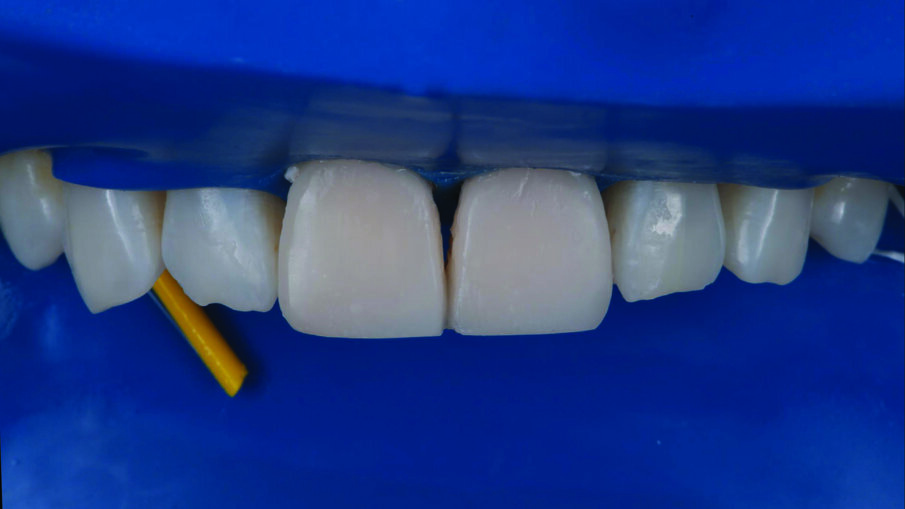

Restorations after polishing using the 3M™ Sof-Lex™ Diamond Polishing System.

Treatment outcome immediately after rubber dam removal. The discolorations were gone, the restorations and the adjacent teeth had a similar shade, and a natural shape was achieved.